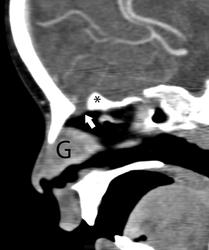

Носовая глиома.

Интраназальная глиома (гетеротопия).

Мария П. Валенсии, Маурисио Кастильо